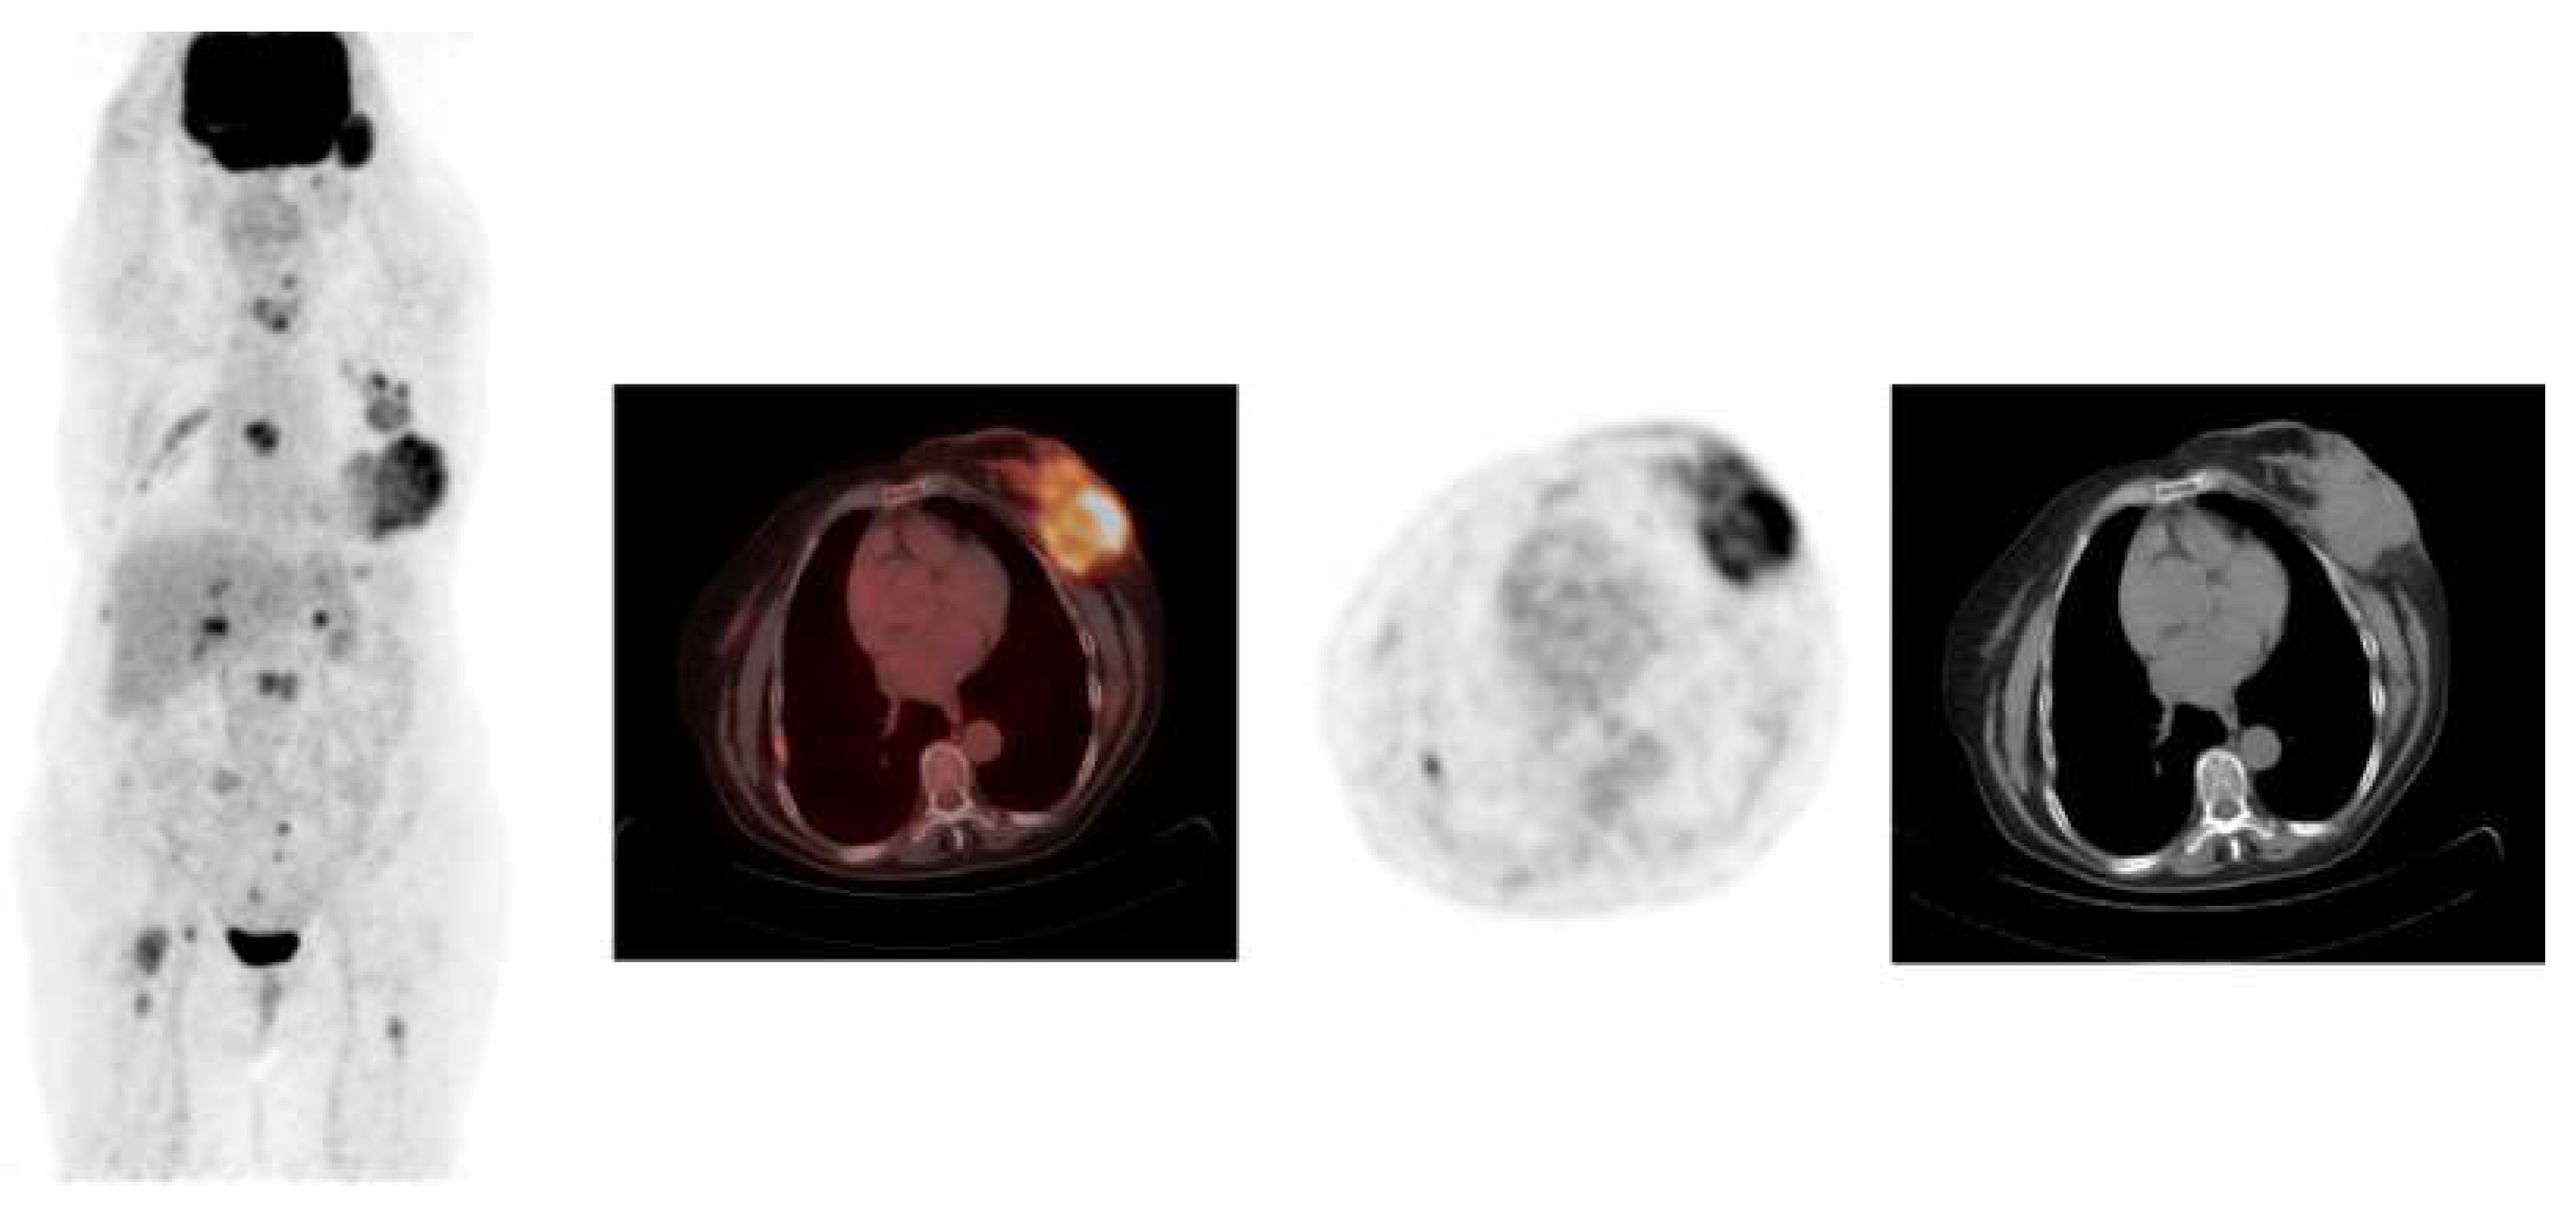

Examples of PEM images of breast cancer are shown in Figure 3 and Figure 4, with the former showing PEM using 3′-deoxy-3′-[18F]-fluorothymidine (18F-FLT) and the latter showing PEM using 68Ga-Trivehexin.